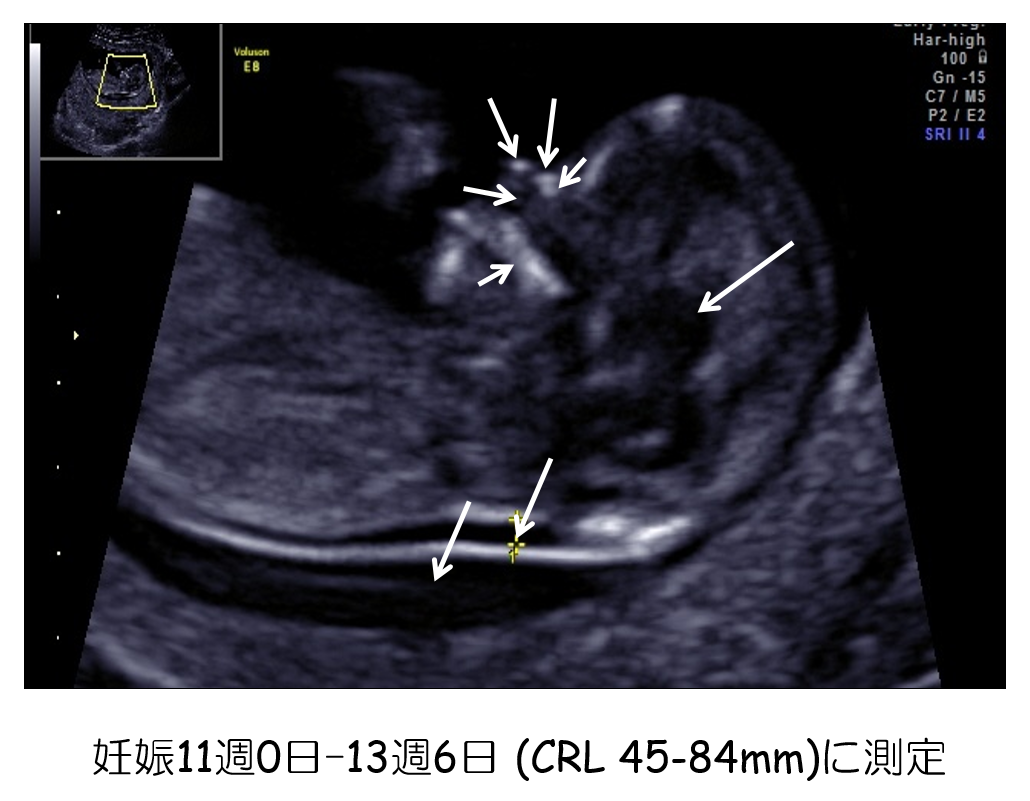

02 妊娠初期 胎児の頸部浮腫 Nt 妊娠11 13週でcheck 深谷産婦人科 医学情報

妊娠初期超音波の出生前診断における役割 Fetal Skeletal Dysplasia Forum

Nt Nuchal Translucency について 出生前検査 Nipt 遺伝カウンセリング 妊婦健診 エコー検査 産科 婦人科 産婦人科

胎児の首のむくみ Nt クリフム夫律子マタニティクリニック